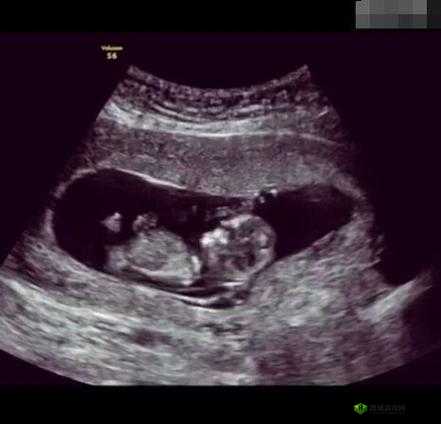

当我们躺在 B 超室的床上,医生突然问“这是第几胎”时,可能很多人都会心生疑惑,这到底是在暗示什么呢?其实,这背后可能有以下这 5 个原因。

原因一:了解孕妇的生育史。医生询问第几胎,首先是为了全面了解孕妇的生育情况。不同的生育次数可能会对本次怀孕和分娩产生不同的影响。如果是头胎,医生可能会更加关注孕妇对于孕期知识的了解程度,给予更详细的指导;而如果是二胎或多胎,医生则需要考虑之前的分娩方式、是否有过孕期并发症等因素,以便更好地评估本次怀孕的风险。

原因二:评估子宫的状态。每一次怀孕和分娩都会对子宫造成一定的影响。多次怀孕可能会导致子宫壁变薄、子宫疤痕等问题。通过了解第几胎,医生可以大致判断子宫的状态,预测可能出现的风险。比如,如果之前有过剖宫产,再次怀孕时就需要特别关注子宫疤痕的厚度和弹性,以避免子宫破裂等危险情况的发生。

原因三:关注胎儿的发育环境。孕妇之前的生育经历可能会对胎儿的发育环境产生影响。例如,如果上一胎有过胎儿发育不良或其他问题,医生会更加谨慎地监测这一胎胎儿的发育情况。了解第几胎可以让医生在评估胎儿健康时更有针对性,及时发现潜在的问题并采取相应的措施。